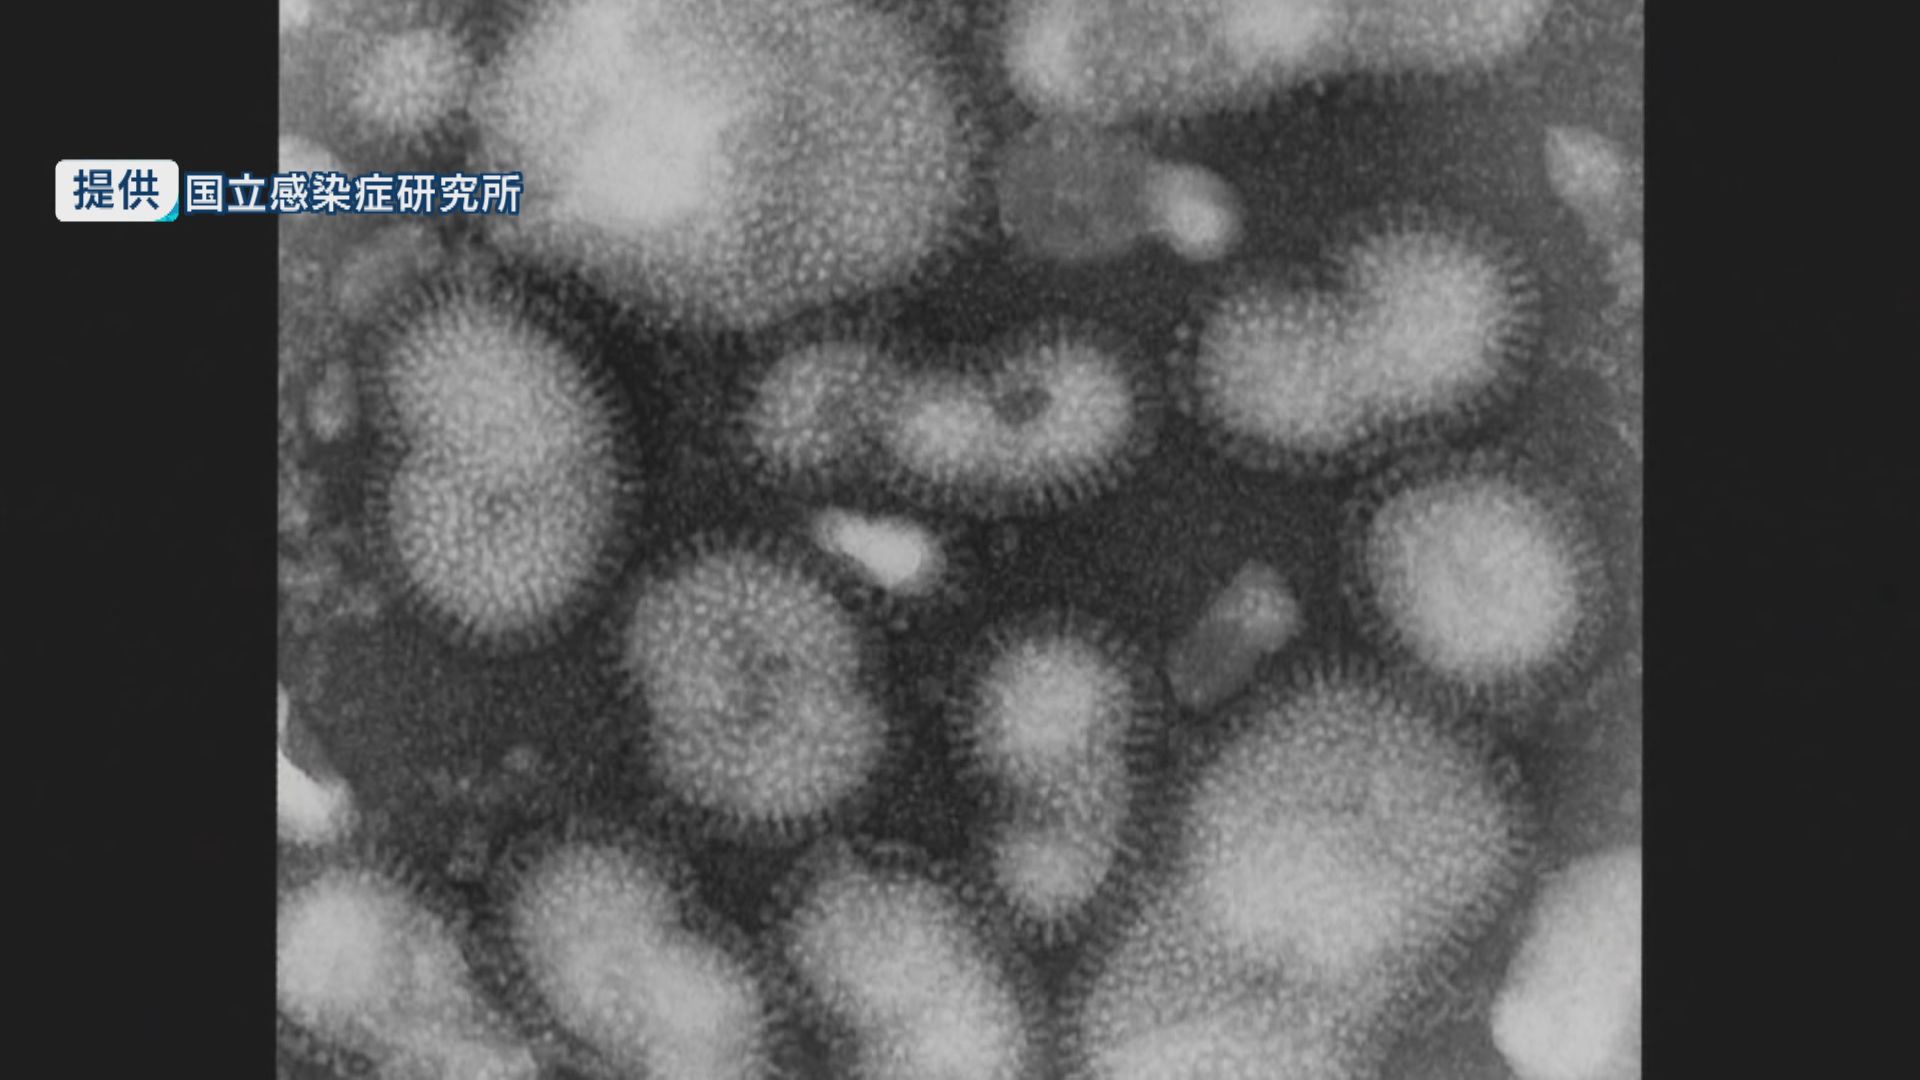

長崎県内のインフルエンザの患者は前の週より減ったものの、流行期は続いていて、引き続きマスクや手洗いなどの対策が必要です。

県感染症情報センターが30日発表した調査報告によりますと、10月20日から26日までのインフルエンザの患者数は114人で、前の週より29人減りました。

しかし定点当たりの報告数は「2.24」で、流行の目安となる「1.0」を上回っていて、地区別でみると県北地区は注意報レベルの「11.0」です。

県ではワクチンの接種に加え、マスクや手洗いなど基本的な予防対策に努めるよう呼びかけています。